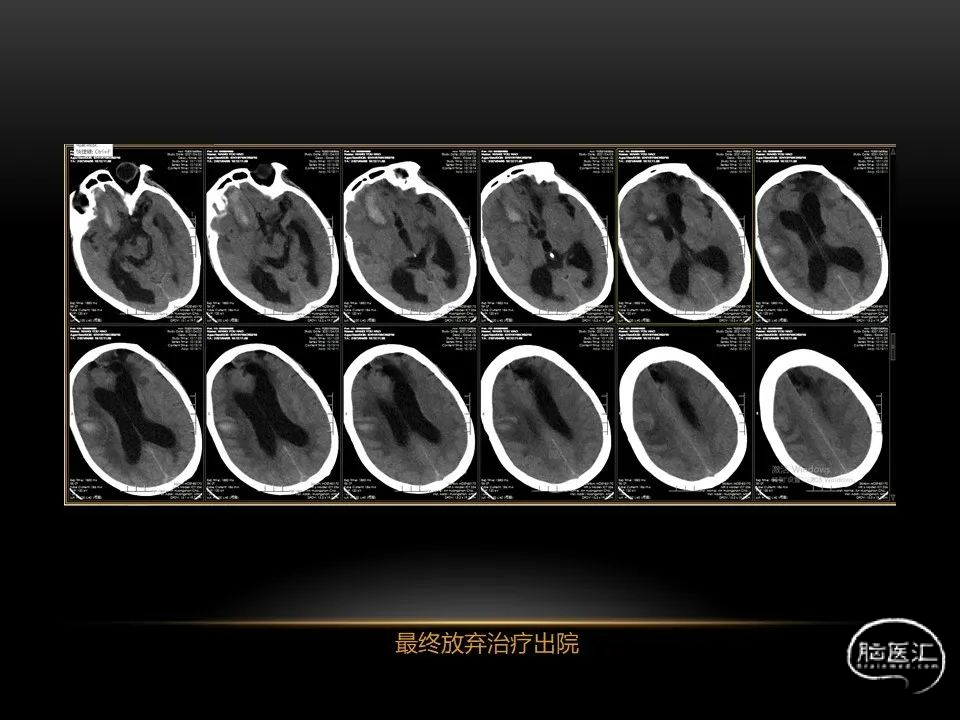

每位患者的病情都不完全一样,唯有通过不断积累、仔细分辨、细心总结,方能沉着应对,为患者造福。本人水平有限,有空就收集一些手头珍贵资料分析分析,总结总结,回味回味,总会发现很多不懂的,总会有新的收获。望老师和朋友们不吝赐教,给我留言交流心得。